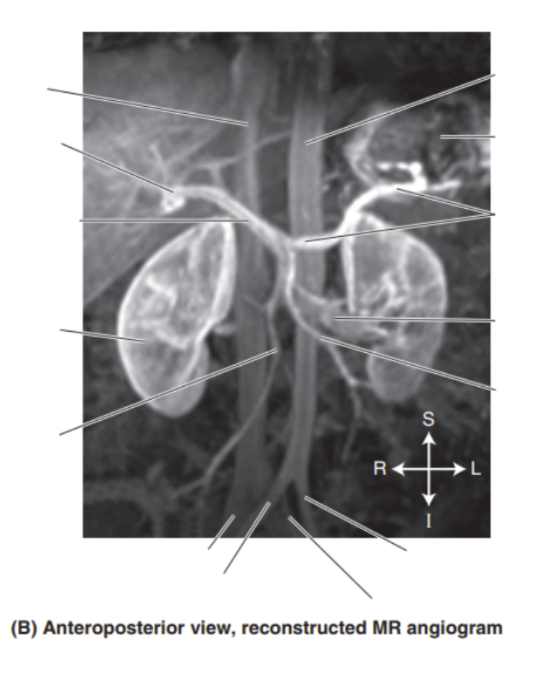

Please label the reconstructed MR angiogram